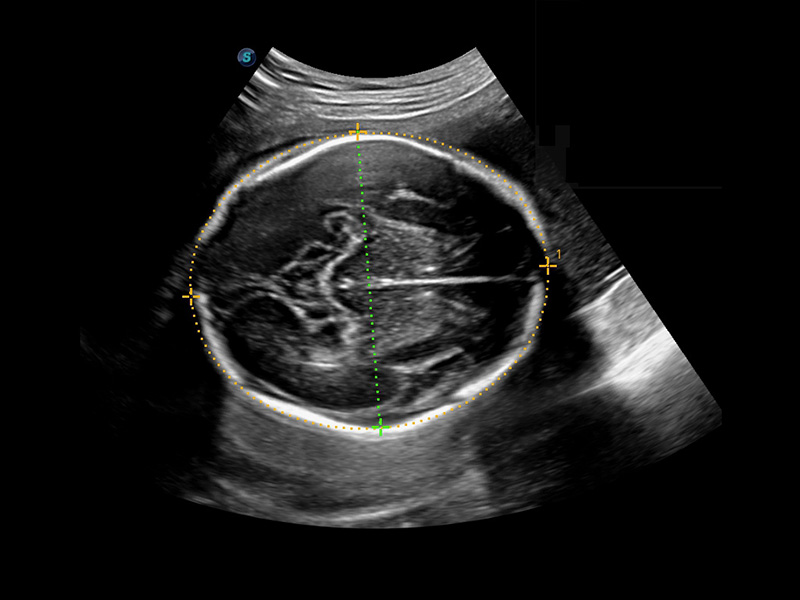

1 OFD(HC): 87,03 mm

HC: 251,00 mm

GA: 27w 1d

HC/AC: 96,13%

2 BPD: 70,56 mm

GA: 28 w 2d

S-Fetus(acq.)

& S-Fetus(meas.)

S-Fetus*

S-Fetus è uno strumento di facile utilizzo che consente il rilevamento completamente automatico e preciso dei piani più significativi e delle misurazioni della biometria fetale, utilizzate frequentemente. Con la modalità cine-loop della testa del feto, S-Fetus è in grado di estrarre i piani standard e visualizzare i risultati della misurazione in un secondo, riducendo notevolmente Il numero di battute e i tempi di lavoro necessari. È progettato per trasformare gli esami ecografici ostetrici in un'esperienza molto più comoda, veloce e piacevole.